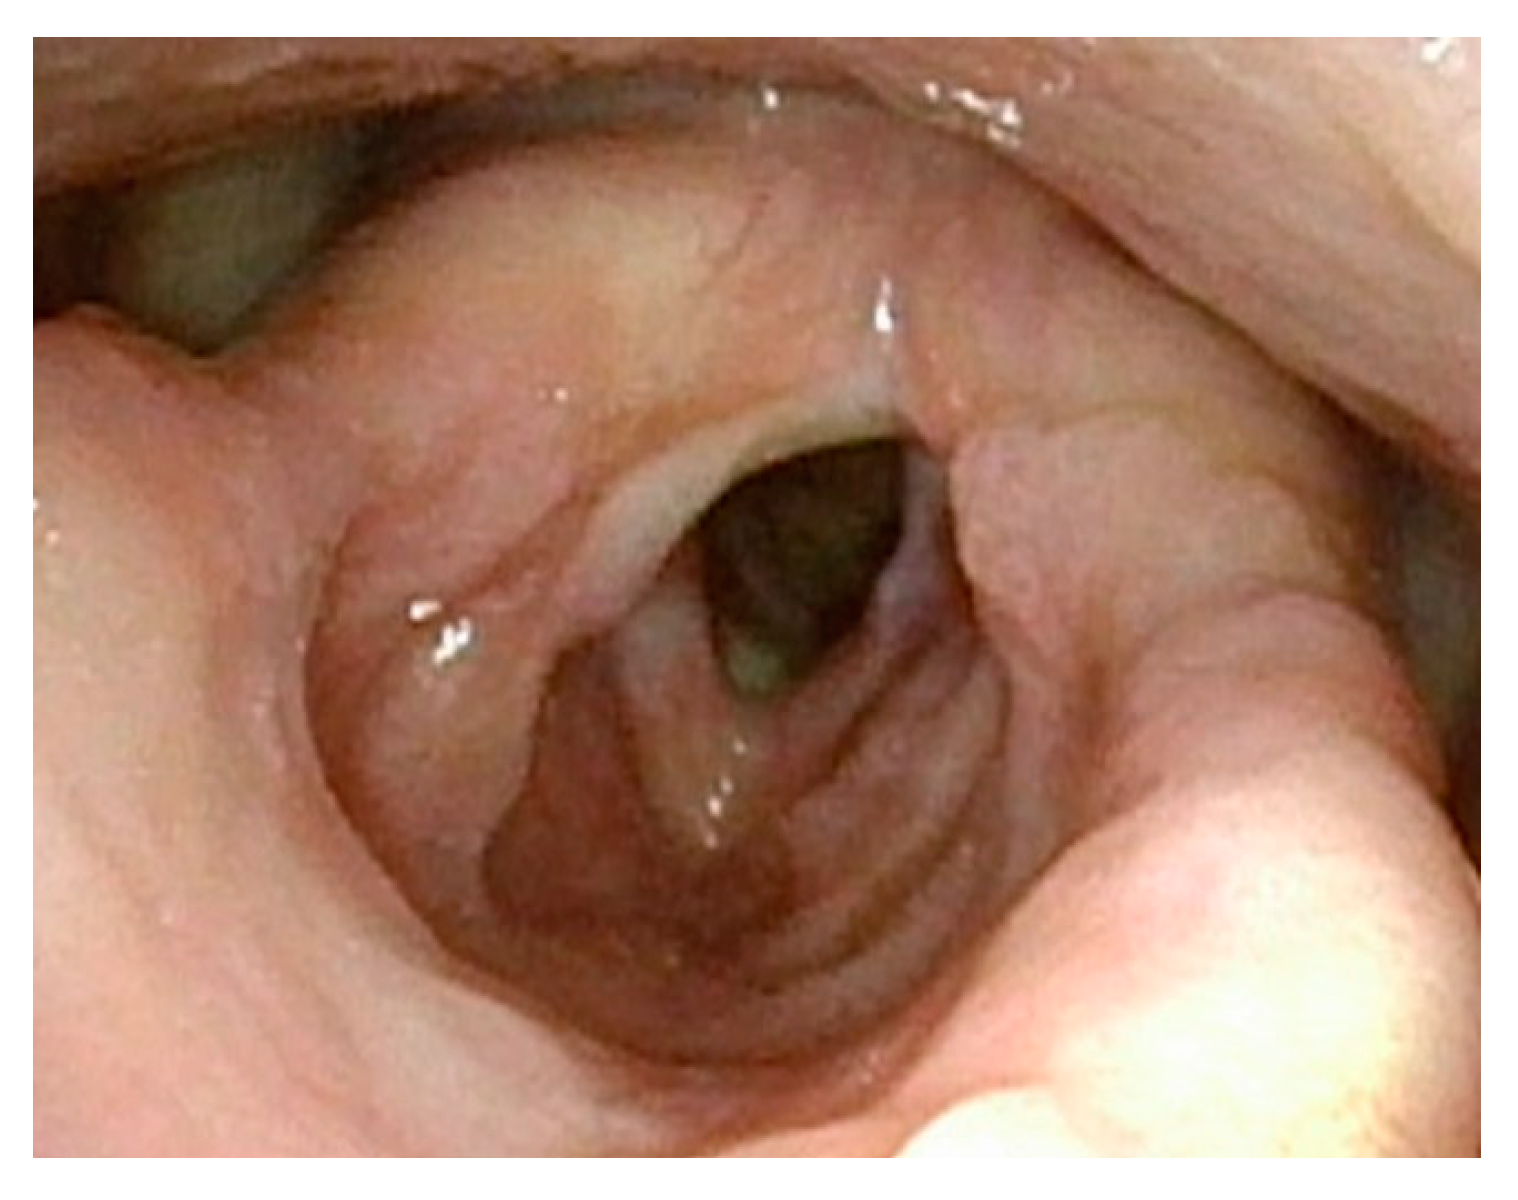

Figure 1 demonstrates a patient who had too aggressive anterior commissure laser treatment. A consequence of this was a very large anterior glottic web. Should this be encountered, the web may be lysed in the midline and steroid-injected (Figure 2). If the web is not the full thickness of the vocal folds, it should be cut with cold steel to help prevent the return of the web during healing. Once healed the web should be significantly improved (Figure 3). Consideration should be given to the dilation of the glottis following lysis.

Figure 1.

Large anterior glottic web with small amount of papilloma on right posterior commissure.